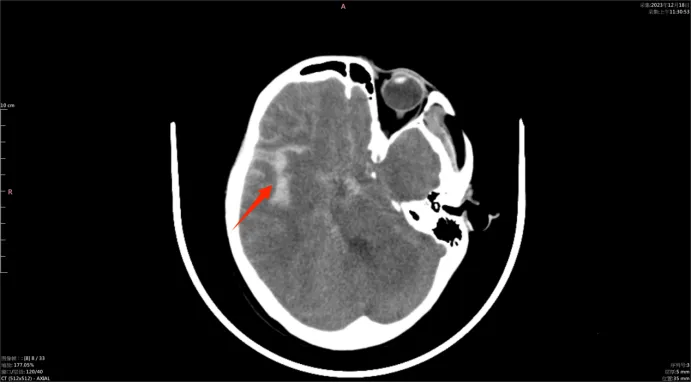

云县人民医院神经内科病例分享:“小手术”解决大问题---神经(脑血管)介入治疗